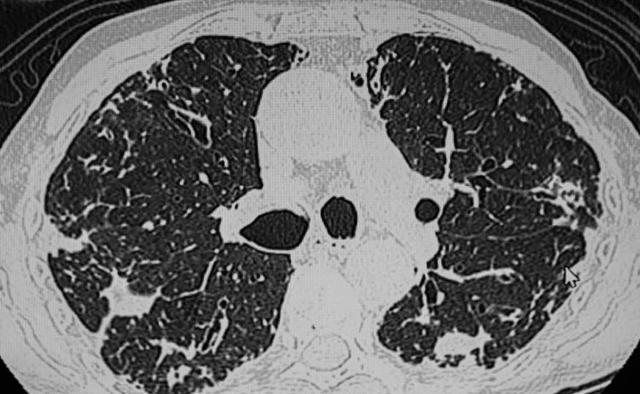

很多患者在罹患肺结节后,身体没有任何不适症状,这种情况下只能通过胸部CT检查来发现结节。

当胸部CT检查普遍后,很多人会被检查结果上的肺结节结果吓到,担心结节会发生癌变。在我国第31个全国肿瘤防治宣传周上,中国抗癌协会整合肿瘤分会青委会主委薛建新明确指出,体检中查出的肺结节95%为良性,只有5%有恶变的可能性。

有这几种特征的肺结节,恶性程度很高,要多加警惕:

? 大小:体积越大的结节危险程度就越高

? 数量:相同性质的结节,数量越多的恶性程度会比数量少的要高

? 长相:结节有毛刺征、分叶状、血管集束征、胸膜凹陷征等特征,恶性程度较高

? 位置:处于肺叶处的结节风险性较高,中下肺叶的则危险程度较低

? 变化:在发现结节后,医生会建议定期进行复查,复查过程中发现结节变大或是形态发生了改变,都要警惕可能是恶变了

? 密度:从危险程度上来看,是混合型>磨玻璃>实性